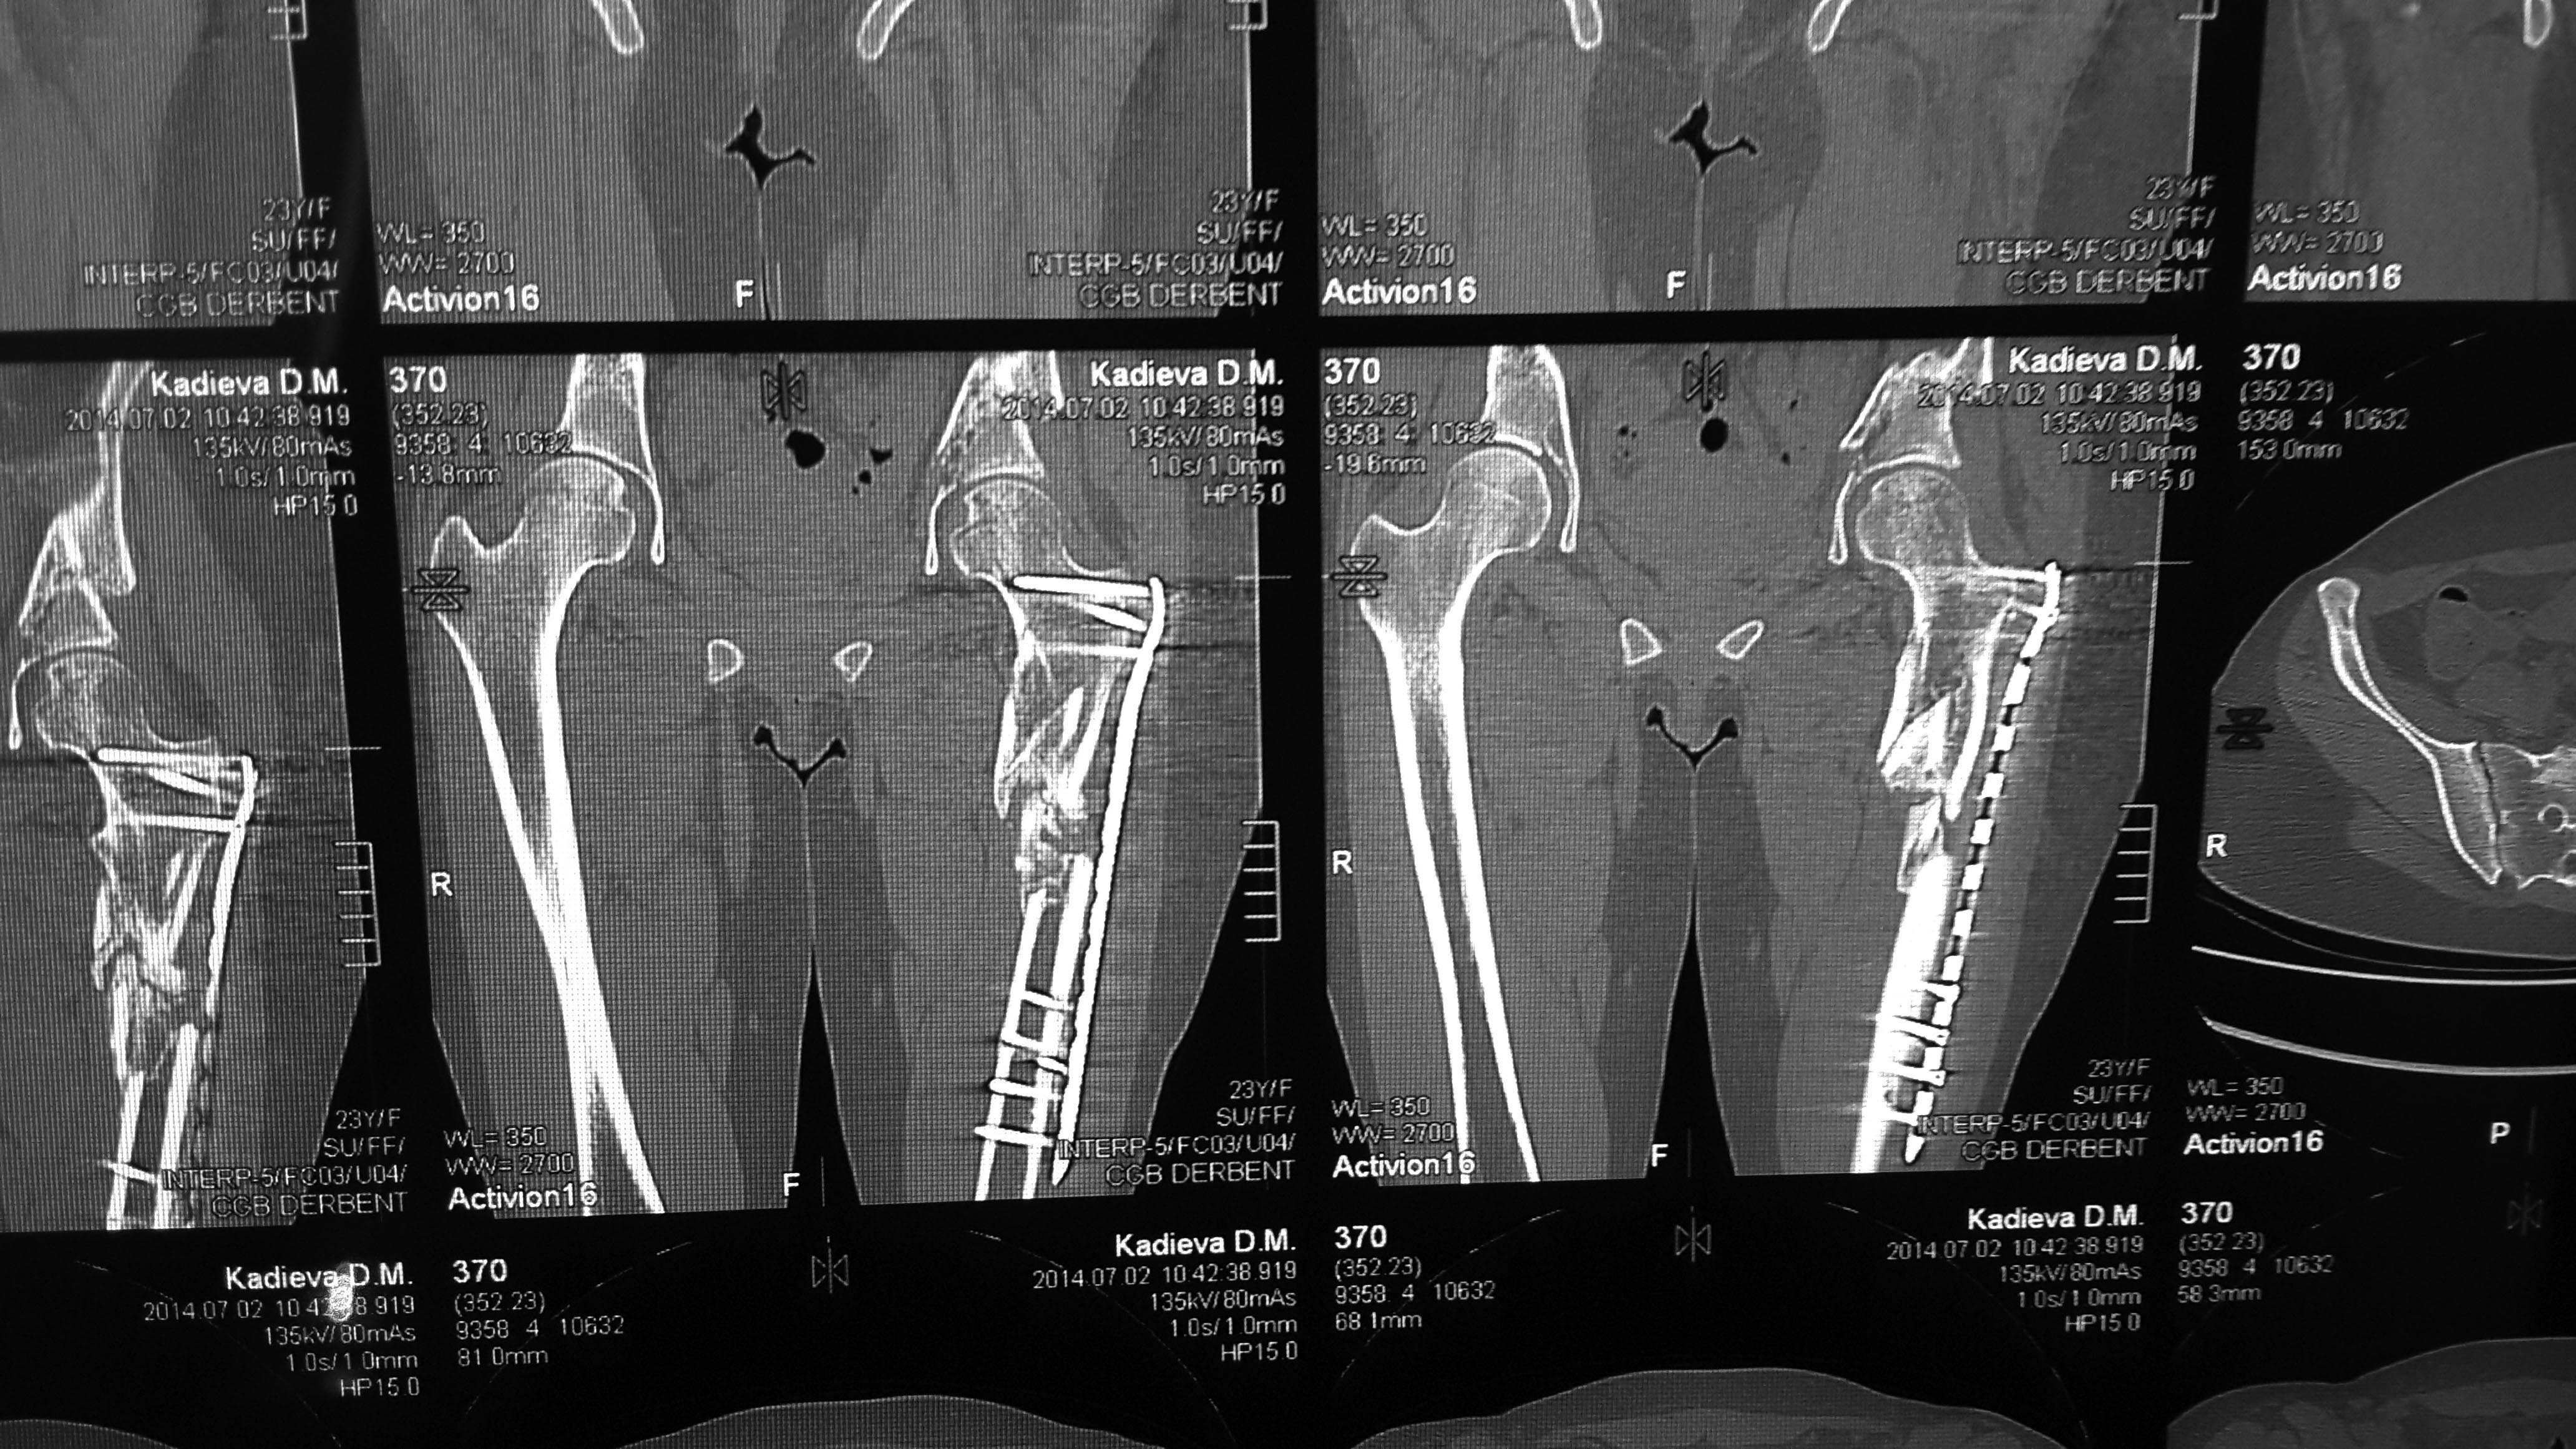

Пациентка К., 23 л., красивая девушка, уроженка одного из удаленных южных регионов России. Травма 31.12.13 в результате ДТП (столкновение а/машин). Находилась на лечении в нашем травматологическом отделении со следующим диагнозом: Сочетанная травма: ОЧМТ: Ушиб головного мозга легкой степени. Перелом передней стенки лобной пазухи со смещением отломков. Перелом латеральной стенки левой орбиты без смещения отломков. Ушибленные раны левого верхнего века. Ушиб левого легкого. Закрытое вертикально-нестабильное повреждение таза: трансфораминальный перелом крестца слева, частичный разрыв левого крестцово-подвздошного сочленения, вертикальный оскольчатый перелом крыла левой подвздошной кости со смещением отломков, поперечный перелом левой вертлужной впадины без смещения отломков. Закрытый многооскольчатый перелом левой бедренной кости в в/3 и с/3 со смещением отломков. Травматический шок II ст.

дальнейшее лечение проходило у нас. Кости таза фиксированы канюлированными винтами и АВФ. Предполагался БИОС бедренной кости, однако из-за отсутствия в больнице современных имплантов

(угадайте с 3-х раз- почему?)и средств у больной был выполнен 22.01.14 малоинвазивный остеосинтез проксимального отдела бедра чем Бог послал (каким-то чудом оказавшаяся у нас дистальная бедренная пластина "Деост", не б/у) (см. снимки)-критика принимается. П/операционный период гладкий. Выписана с рекомендацией начать нагрузку на конечность через 12 недель после операции. Убыла на малую родину. Дальнейшая связь поддерживалась по e-mail. Рекомендации она не соблюдала: нагрузку на ногу начала недели 3 назад. Сейчас беспокоят боли в одноименном коленном суставе, отека нет, болей в месте перелома нет, анализы в норме, незначительное ограничение движений в ТБС. По месту жительства выполнила КТ (снимки и описание в приложении). Местные коллеги утверждают, что необходимо сделать реостеосинтез, но сами не берутся. Вопрос больше от пациентки: "Делать ли повторную операцию сейчас, или некоторое время походить с полной нагрузкой и сделать контроль, а там решать?"